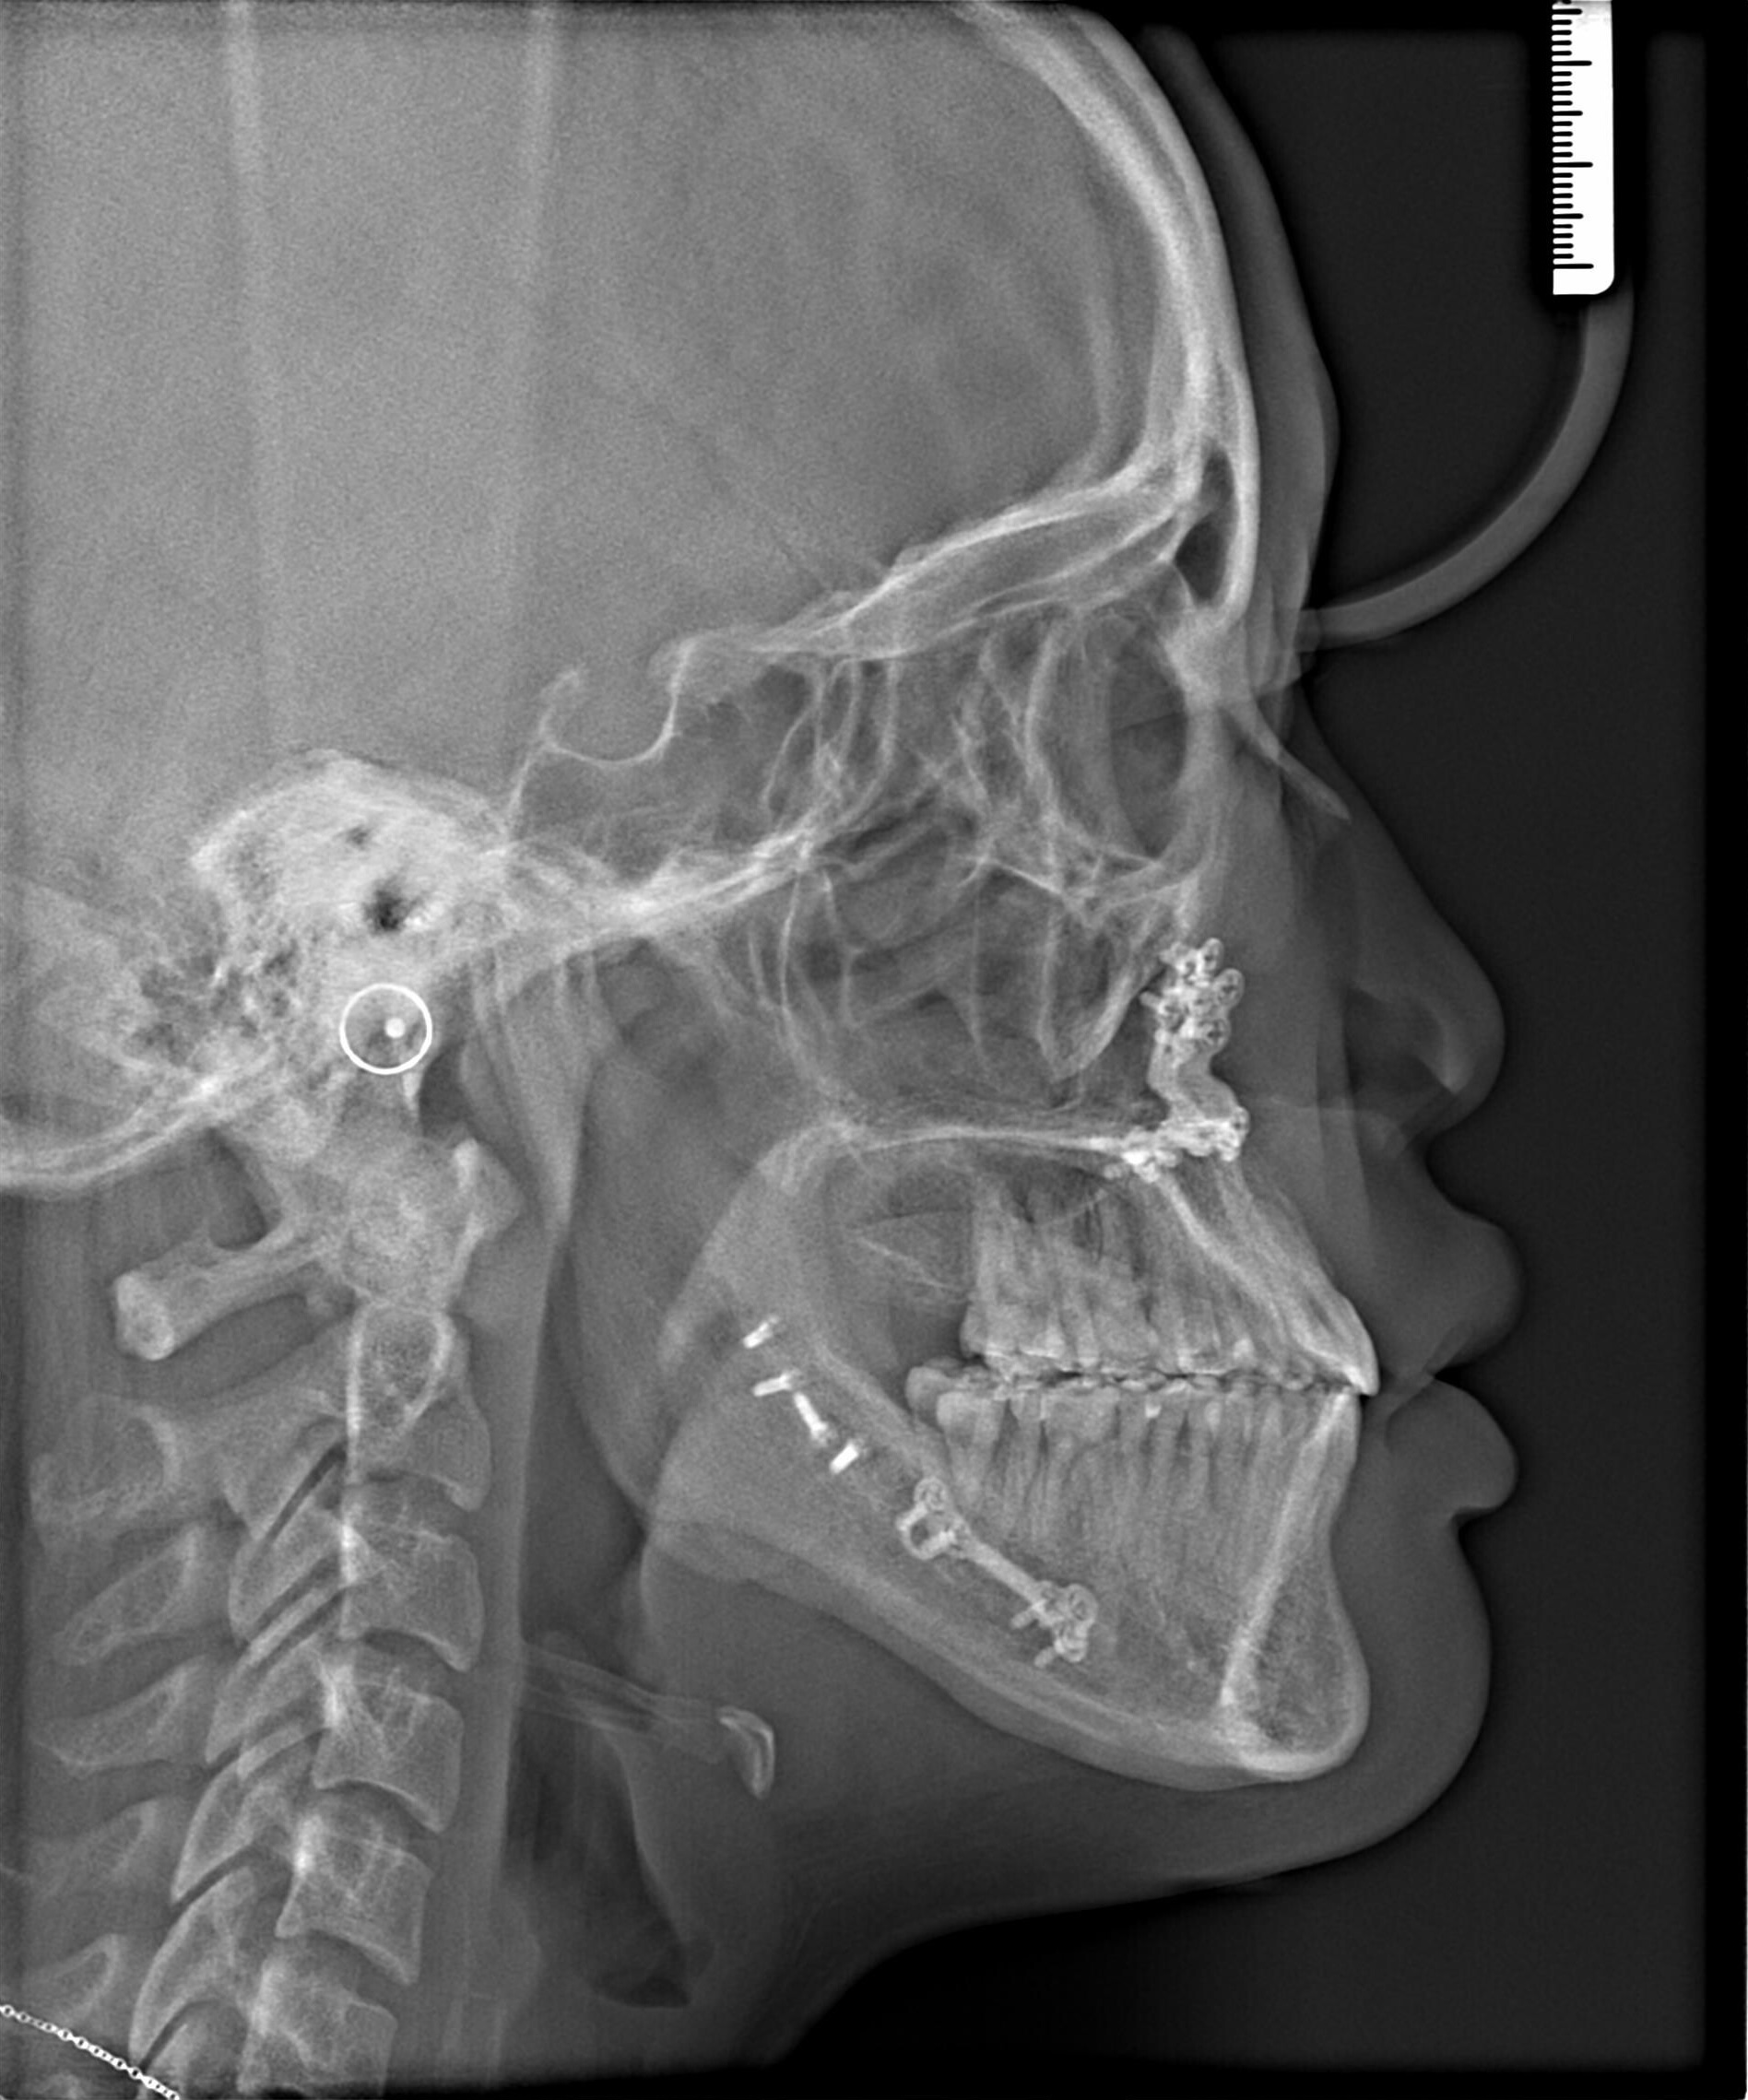

Before Metal Self-Ligating Braces & Orthognathic Surgery: The Surgical Comeback case study at AOB Orthodontics in Las Vegas. Clinical diagnosis: showing a severe skeletal imbalance that braces alone could not correct. Before

Before orthodontic x-ray: Cephalometric profile before Metal Self-Ligating Braces & Orthognathic Surgery showing skeletal relationship. Before

This case began with a severe skeletal imbalance that braces alone could not correct. The patient presented with a significant Class III bite, asymmetric mandibular prognathism, anterior crossbite, and midline deviation. Because the jaw relationship was the root of the problem, a combined orthodontic and surgical approach was required to achieve the best stable, long-term result.

This transformation was designed with intention. Dr. Benson used braces to sculpt alignment and prepare the bite, then collaborated with an oral surgeon to reposition the mandible through orthognathic surgery. The result: a stable bite, restored facial balance, and symmetry achieved.